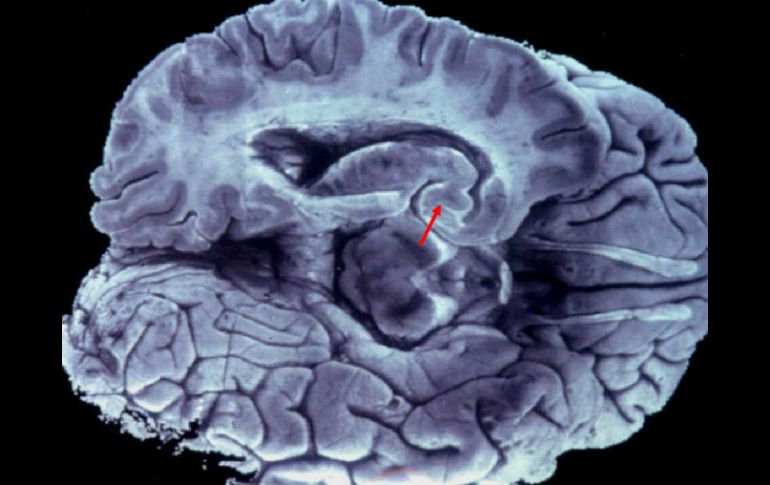

Tecnología | Una mujer china ex profesora de inglés sólo es capaz de comunicarse en ese idioma Paciente de infarto cerebral pierde aptitud de hablar su idioma natal Una mujer china ex profesora de inglés sólo es capaz de comunicarse en el idioma que enseñó por mucho tiempo Por: NTX 3 de febrero de 2015 - 19:25 hs Esta condición no es frecuente pero tampoco inusual, pues casos similares se han reportado en todo el mundo. EFE / ARCHIVO BEIJING, CHINA (03/FEB/2015).- Una ciudadana china de 94 años de edad, ex profesora de inglés, perdió su habilidad de hablar en su lengua natal después de sufrir un infarto cerebral y sólo es capaz de comunicarse en el idioma que enseñó por mucho tiempo. Liu Jiayu, de la sureña provincia de Hunan, sufrió un accidente cerebrovascular isquémico causado por una obstrucción en los vasos sanguíneos, lo cual le causó daños en la parte del cerebro relacionada con el lenguaje materno, informaron los neurólogos que la atienden. Los médicos afirman que la condición de Liu no es frecuente, pero tampoco inusual, pues casos similares se han reportado en todo el mundo, incluido el Síndrome de Acento Extranjero, y suelen ocurrir después de que un paciente sufre apoplejía u otro trauma cerebral. Algunas veces se han registrado situaciones en las que personas que aprendieron y están aprendiendo un segundo idioma, serán más capaces de hablar éste después de sufrir una lesión cerebral, dicen los especialistas, citados en reportes de la televisión local. Explican que la información relacionada con la lengua materna de una persona se almacena en el lado izquierdo del cerebro, mientras que la capacidad de aprender y hablar un segundo idioma en el lado derecho. Imágenes de la televisión de Hunan difundieron imágenes de la mujer en cama respondiendo a preguntas sencillas en idioma inglés. "Ella me saluda en la mañana usando frases en inglés, y después de comer me agradece en inglés", relata una enfermera. Liu sufre de parálisis de todos sus miembros y dificultad en sus funciones de lenguaje, refiere el doctor Li Yanfang. Señala que ha habido casos raros en los que los pacientes desarrollan un acento diferente después de un accidente cerebrovascular, pero el caso de Liu parece diferente porque sólo habla un lenguaje que aprendió. Los expertos dicen que la lengua china es compleja y requiere el uso de ambas partes del cerebro, mientras que el idioma inglés sólo utiliza uno de los lados, lo cual explicaría la condición de la ex profesora. En 2010, se reportó el caso de una mujer de Reino Unido que se despertó hablando con un acento chino tras sufrir raras migrañas hemipléjicas esporádicas. Temas Ciencia médica Cerebro Idiomas Curiosidades Lee También ¿Cuáles son los beneficios de tomar jugo de betabel y cómo se prepara? ¿Qué frutas pueden comer los perros? Estos son algunos remedios caseros para dormir mejor Conmociones cerebrales, la cuarta lesión más frecuente en partidos de la Conmebol Recibe las últimas noticias en tu e-mail Todo lo que necesitas saber para comenzar tu día Registrarse implica aceptar los Términos y Condiciones